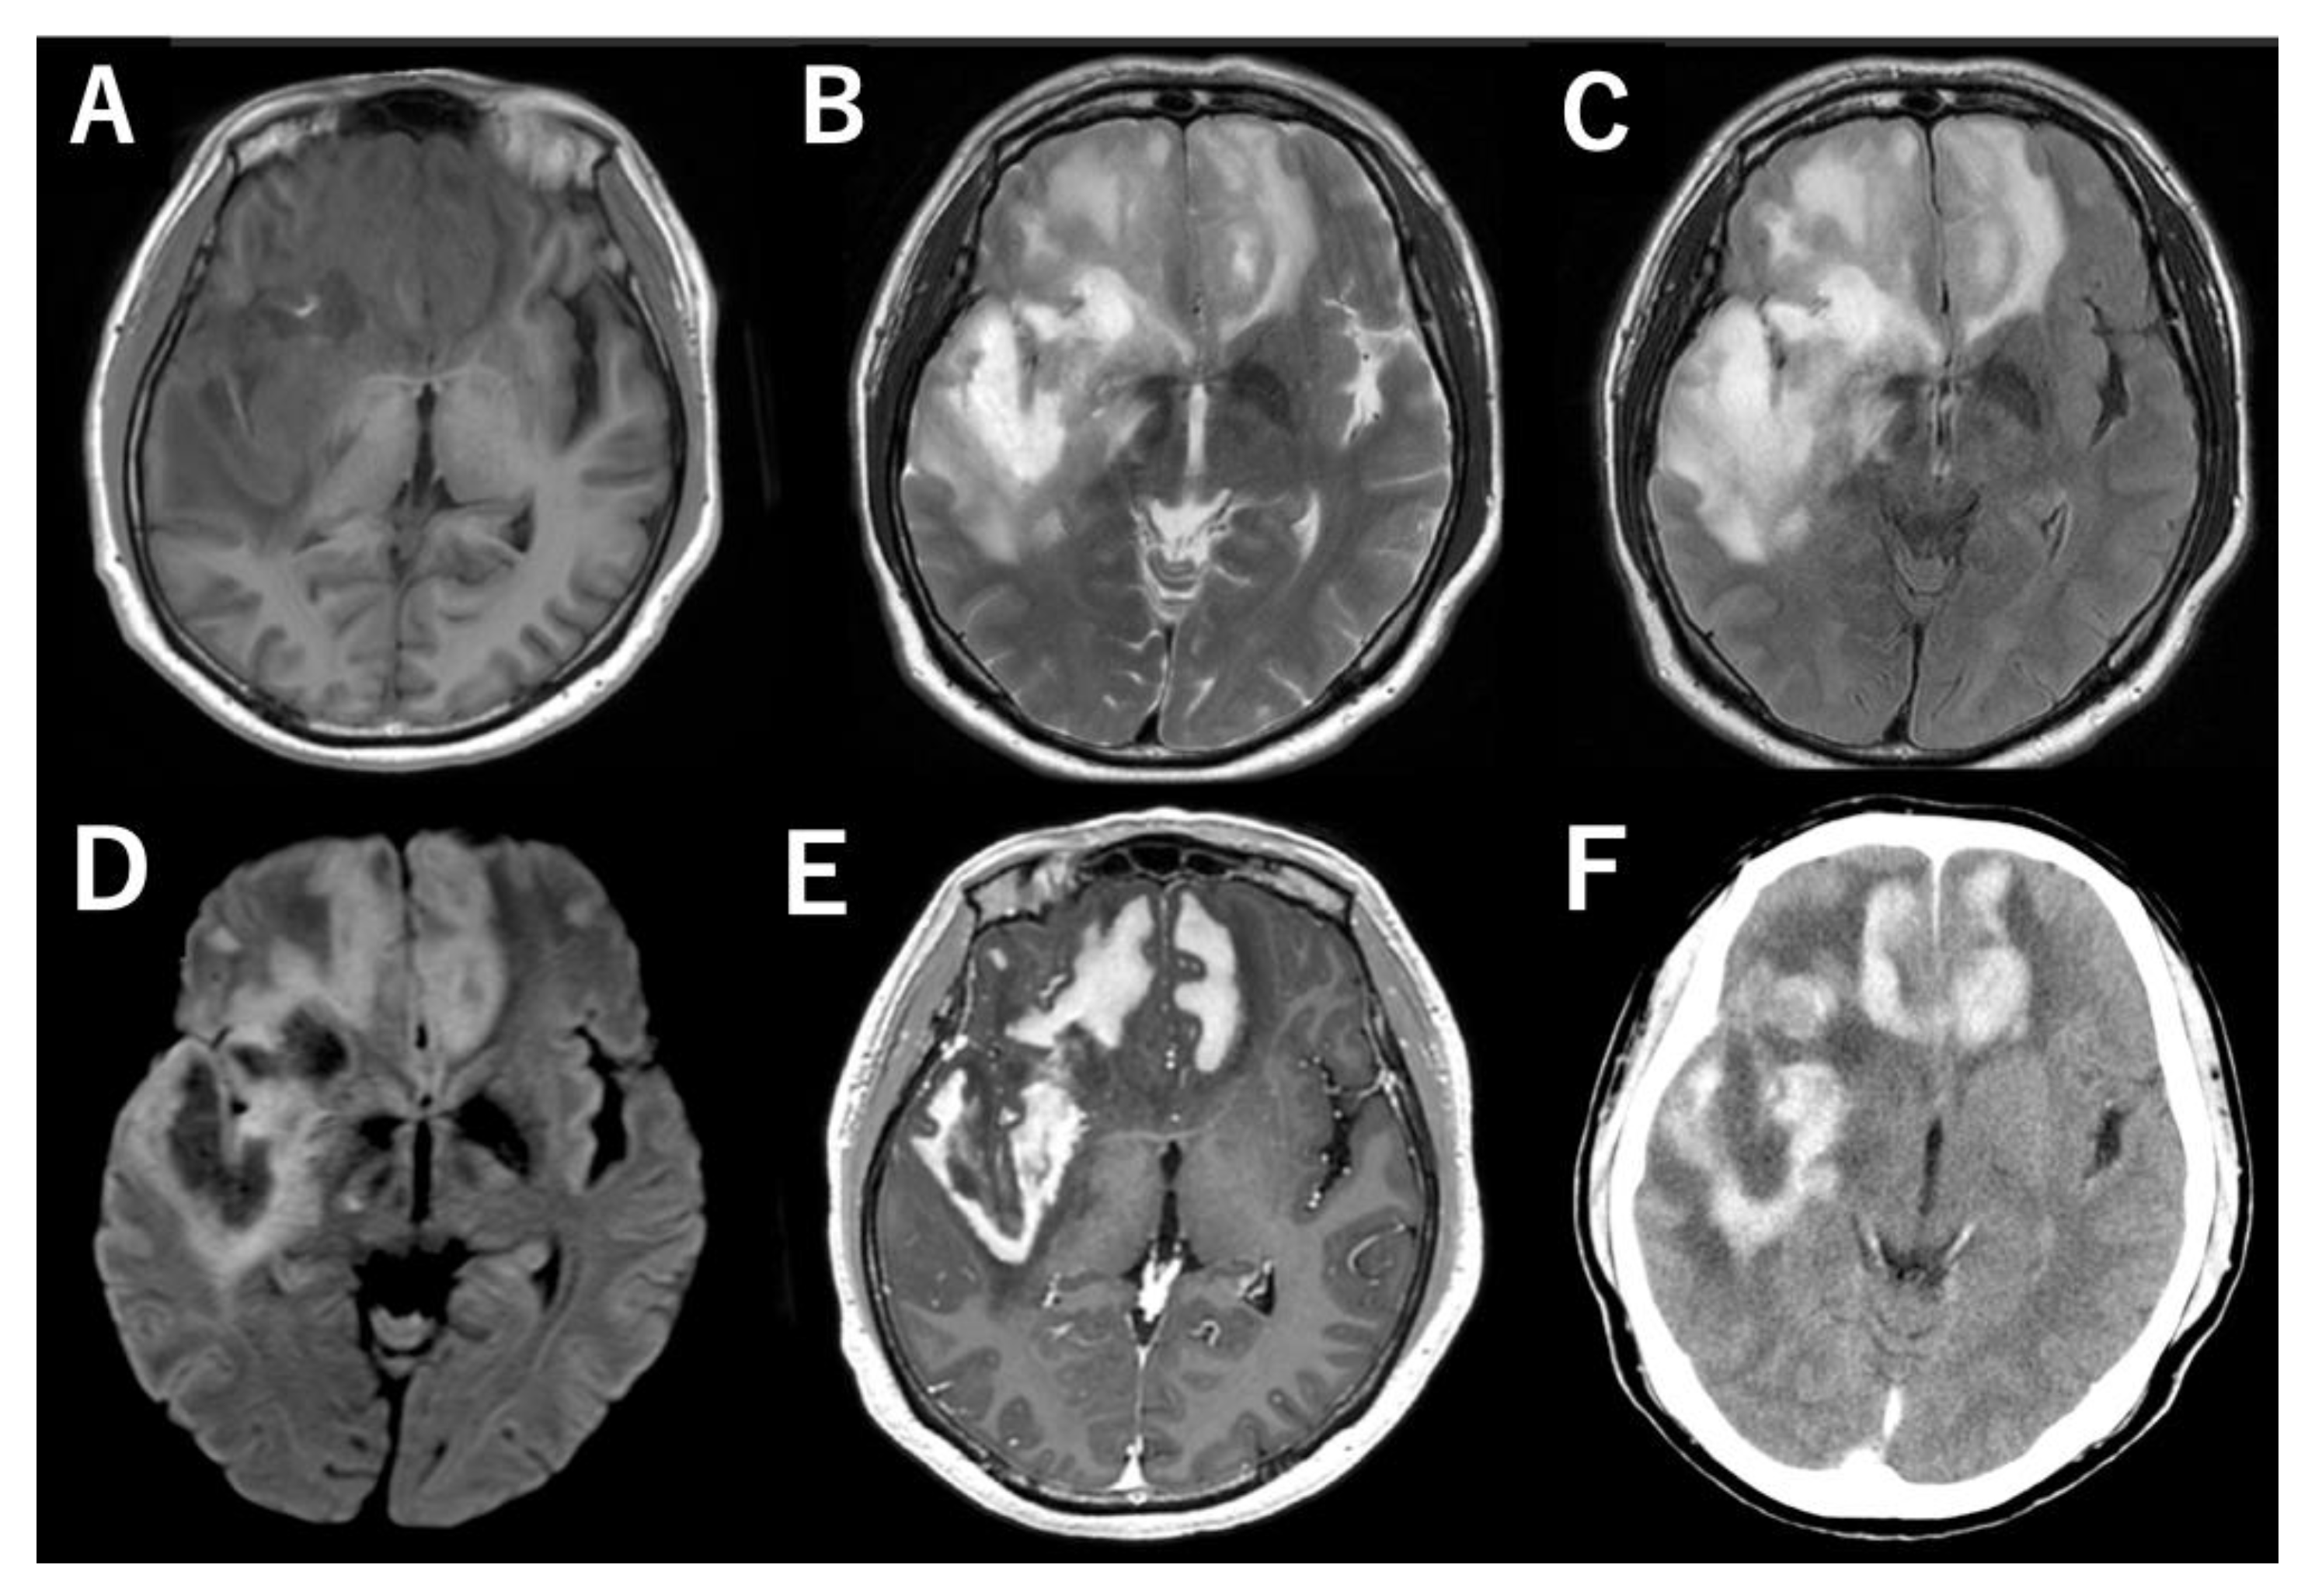

2. Case Presentation